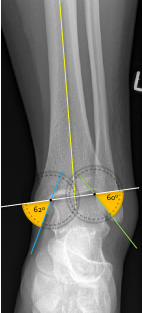

Q what is the left angle of this radiograph? and what is the average + range?

A: Tibial Angle (Ankle)

assesses the medial angle between the medial malleolus and the talus lines. The average is 53°, with a range of 45-65°.

Q what is the right angle of this radiograph? and what is the average + range?

A: Fibular Angle

assesses the lateral angle between the lateral malleolus and the talus lines. The average is 52°, with a range of 43-63°.

Q what is the name of this measurement? and what is the average + range?

A: Tibiotalar Slant

assesses the alignment of the distal tibia and talus. The range is 0-6°.